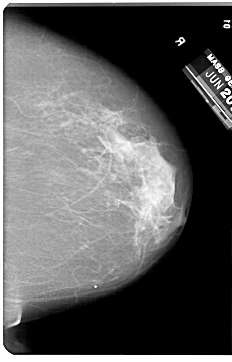

A_1329_1.RIGHT_CC

RIGHT_CC LINES 6871 PIXELS_PER_LINE 4396 BITS_PER_PIXEL 12 RESOLUTION 43.5 NON_OVERLAY